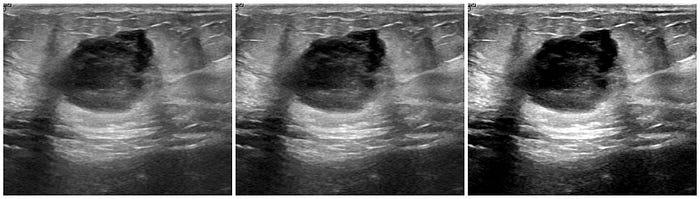

In medical imaging, where precision is crucial, noise should be carefully considered to avoid obscuring important diagnostic details. There are different types of noise modalities that can be introduced, however I'll only be going over the gaussian noise and impulse noise (salt & pepper) in this post.

Impulse noise is a type of noise that affects individual pixels by setting them to either the maximum intensity (salt) or the minimum intensity (pepper) hence the name "Salt and Pepper Noise". In medical imaging, salt-and-pepper noise can simulate abrupt signal drops (black pixels) or spikes (white pixels) that might result from sensor malfunctions, motion artifacts, or other irregularities in the imaging process.

A Gaussian blur is a type of image blurring that involves convolving the image with a Gaussian distribution. This process smoothens the image by reducing high-frequency noise and fine details, which results in a 'blurred' like appearance. The extent of blurring is controlled by the standard deviation (sigma) of the Gaussian distribution. A larger sigma value leads to a stronger blur effect, and a smaller value results in milder blurring.

Much like other augmentation methods, in medical imaging, blur augmentation can simulate the effects of motion or imperfections in imaging devices. For instance, when capturing an MRI or CT scan, patient movement or slight vibrations can cause blurring in the resulting images.